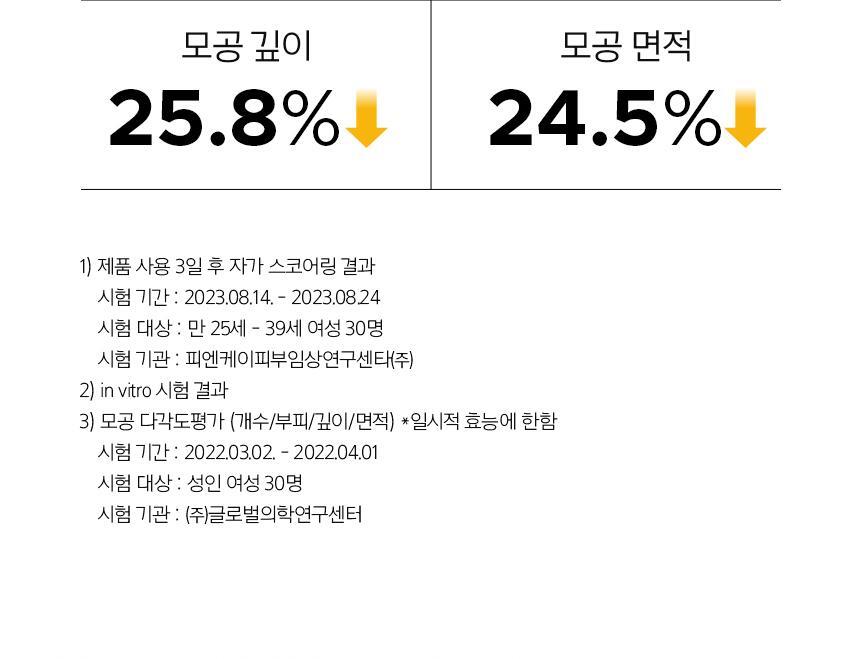

Dès 3 jours, votre peau paraît plus lisse, éclatante et affinée. En seulement 4 semaines, les signes du vieillissement s’estompent, laissant une peau d’apparence 10 mois plus jeune. Sa texture légère pénètre rapidement et agit en profondeur pour améliorer l’élasticité de la peau, tout en garantissant une tolérance optimale même pour les peaux sensibles.

- Réduit l’apparence des pores